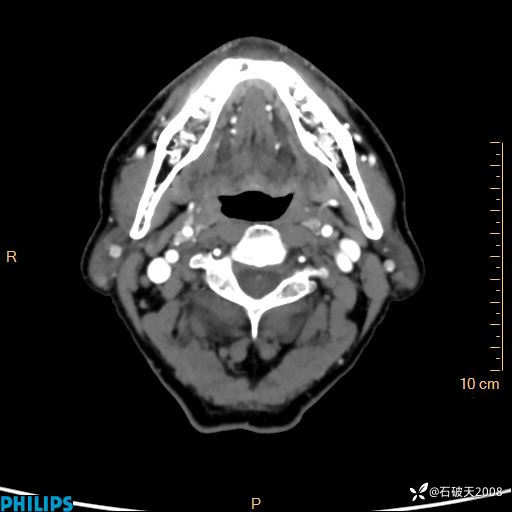

动脉期